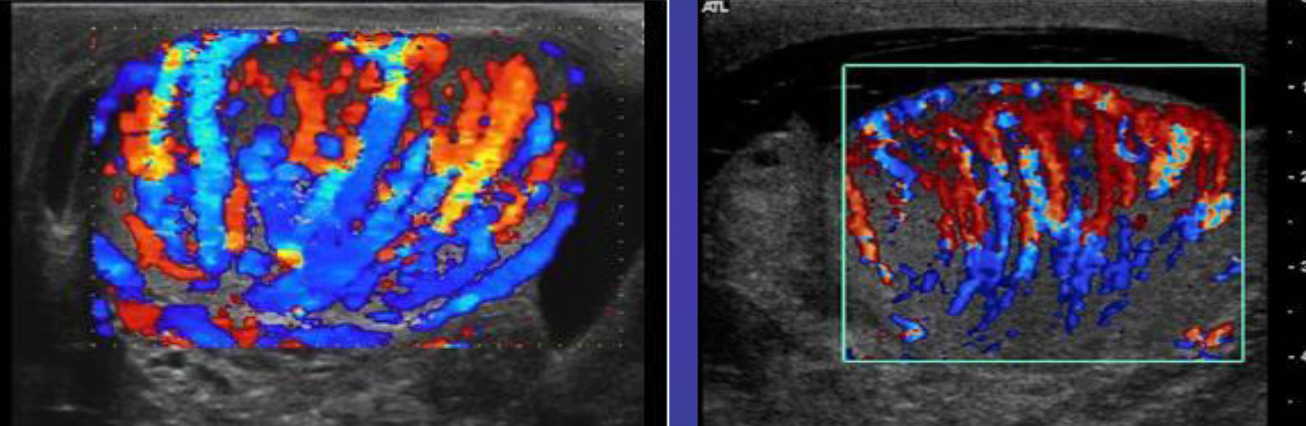

A man presents with testicular atrophy and infertility

Ultrasound of the scrotum Dilated pampiniform veins can be seen within the left scrotum. Doppler sonography (image b) shows the venous reflux. These findings are characteristic of varicocele.

Patient presented with scrotal pain

and swelling - Ranges from mild tenderness to a severe febrile process with acute unilateral scrotal pain. -

A. Give the name of imaging examination. Color Doppler ultrasound

B. Describe the abnormality imaging shows Reactive hydrocele and scrotal wall thickening , edematous epididymis and shows increase vascularity on Doppler

C. What is the most probable diagnosis in the ? Epididymitis

A. Give the name of imaging examination.

*Color Doppler ultrasound is the gold standard investigation.

B. Describe the abnormality

- Hypoechogenicity: Focal or diffuse

- Hypervascularity: Focal or diffuse

- Swelling - Scrotal wall thickening + Scrotal pain and swelling

C. What is the most probable diagnosis in the ? Orchitis

Color Doppler ultrasound of both testes (transverse plane) of a 14-year-old boy

B. Describe the abnormality woke up with acute right scrotal pain - The right testis shows intratesticular flow slightly reduced compared to the left testis

C. What is the most probable diagnosis ? These findings are consistent with testicular torsion